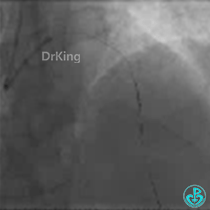

计划采用主支血管LAD支架植入,D1近段药物球囊扩张。

1. 心脏重构是心衰的基础,该患者入院后评估考虑缺血引起的心脏重构,积极治疗血管狭窄是基础;

2. 合理规范的药物治疗是治疗心力衰竭的基石,“金三角”是基石的中流砥柱;

3. 对于特殊病变必须有应变的能力,双枪微导管辅助导丝翻转技术在此类病变中犹如利器,能起到高效通过的机会;

4. 规范治疗后,患者的预后良好。